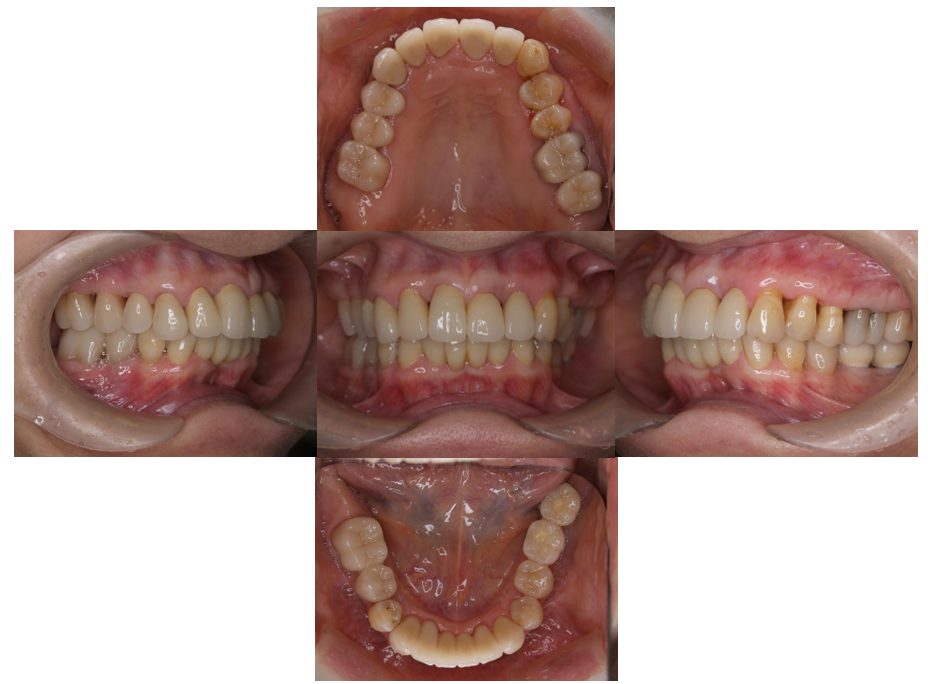

矯正治療・根管治療・補綴治療の症例紹介(三隅歯科クリニック)

三隅 賢祐(三隅歯科クリニック)

症例詳細

| 主訴 | 過去作成した右下の被せ物がずれて入っており、たまに腫れる。歯並びも気になる。 |

| 治療内容 | 矯正治療を行いました。 |

| 治療費 | 800,000円(税込み) |

| 治療期間 | 2年半(矯正治療期間 2年) |

| 治療回数 | 30回 |

| 想定されたリスク | 術前に基礎資料を整え分析し、セットアップモデル等でシミュレーションをしておかないと、予定通りの治療が行えないリスクがあった。 |